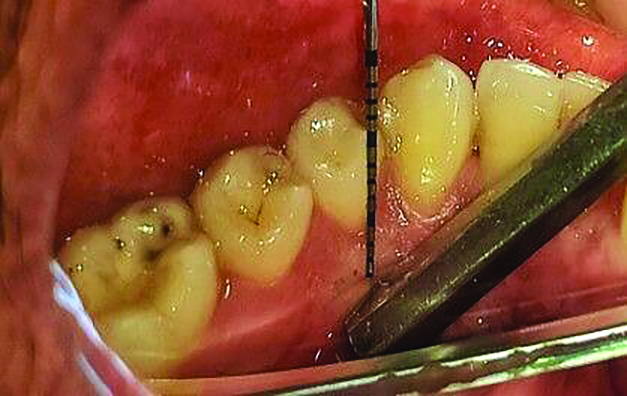

The MGJ was delineated by the visual method and the roll method following clinical examination in dental chairs appropriately equipped. Visual assessment relies on identifying the color difference between the gingiva and alveolar mucosa. The mucosa beyond the MGJ typically appears darker red compared to the AG, helping to demarcate the MGJ. The rolling probe method entails pushing the neighboring alveolar mucosa coronally with the blunt end of a probe. It is a functional assessment method that aids in determining the boundary between gingiva and movable mucosa.10 The probing sulcus depth was subtracted from the measured KG width at the mid-lingual aspect of each tooth to determine the width of AG, and all fractional measurements were rounded off to the nearest whole number of millimeters (Figure 1 through Figure 3).

Fig 3 = determining width of keratinized gingiva.

Figure 3

Fig 4 through Fig 6. Lingual attached gingiva in a male subject: Fig 4 = left side.

Figure 4

Fig 5 = middle.

Figure 5

Fig 6 = right side.

Figure 6